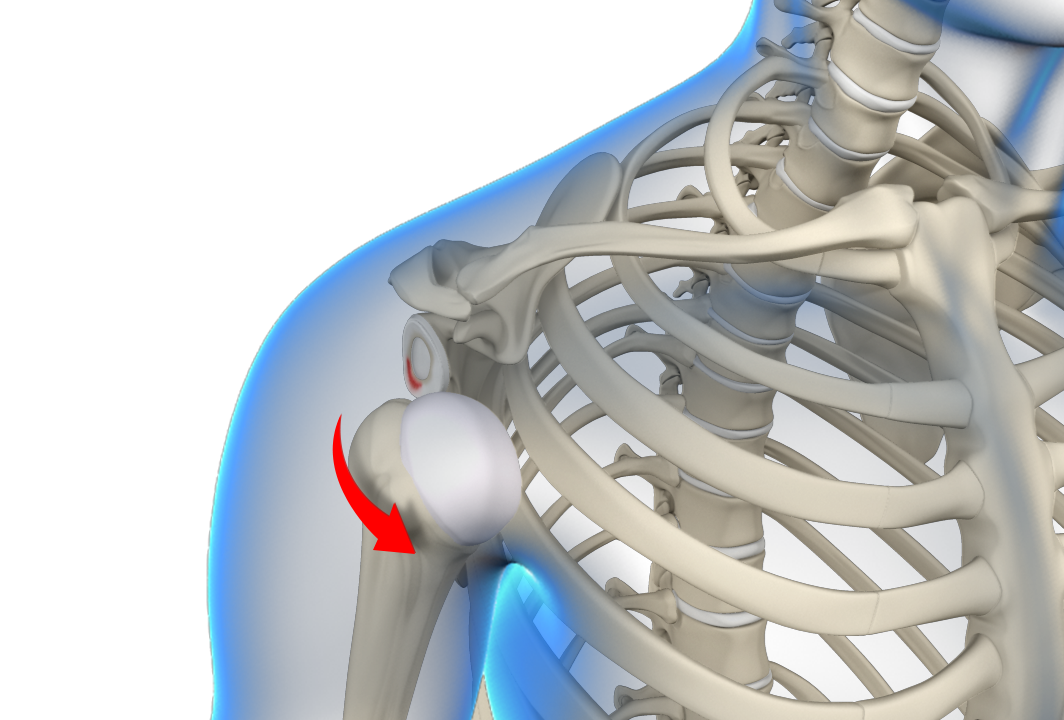

Shoulder Dislocation

Sports that involve overhead movements and repeated use of the shoulder at your workplace may lead to sliding of the upper arm bone from the glenoid.